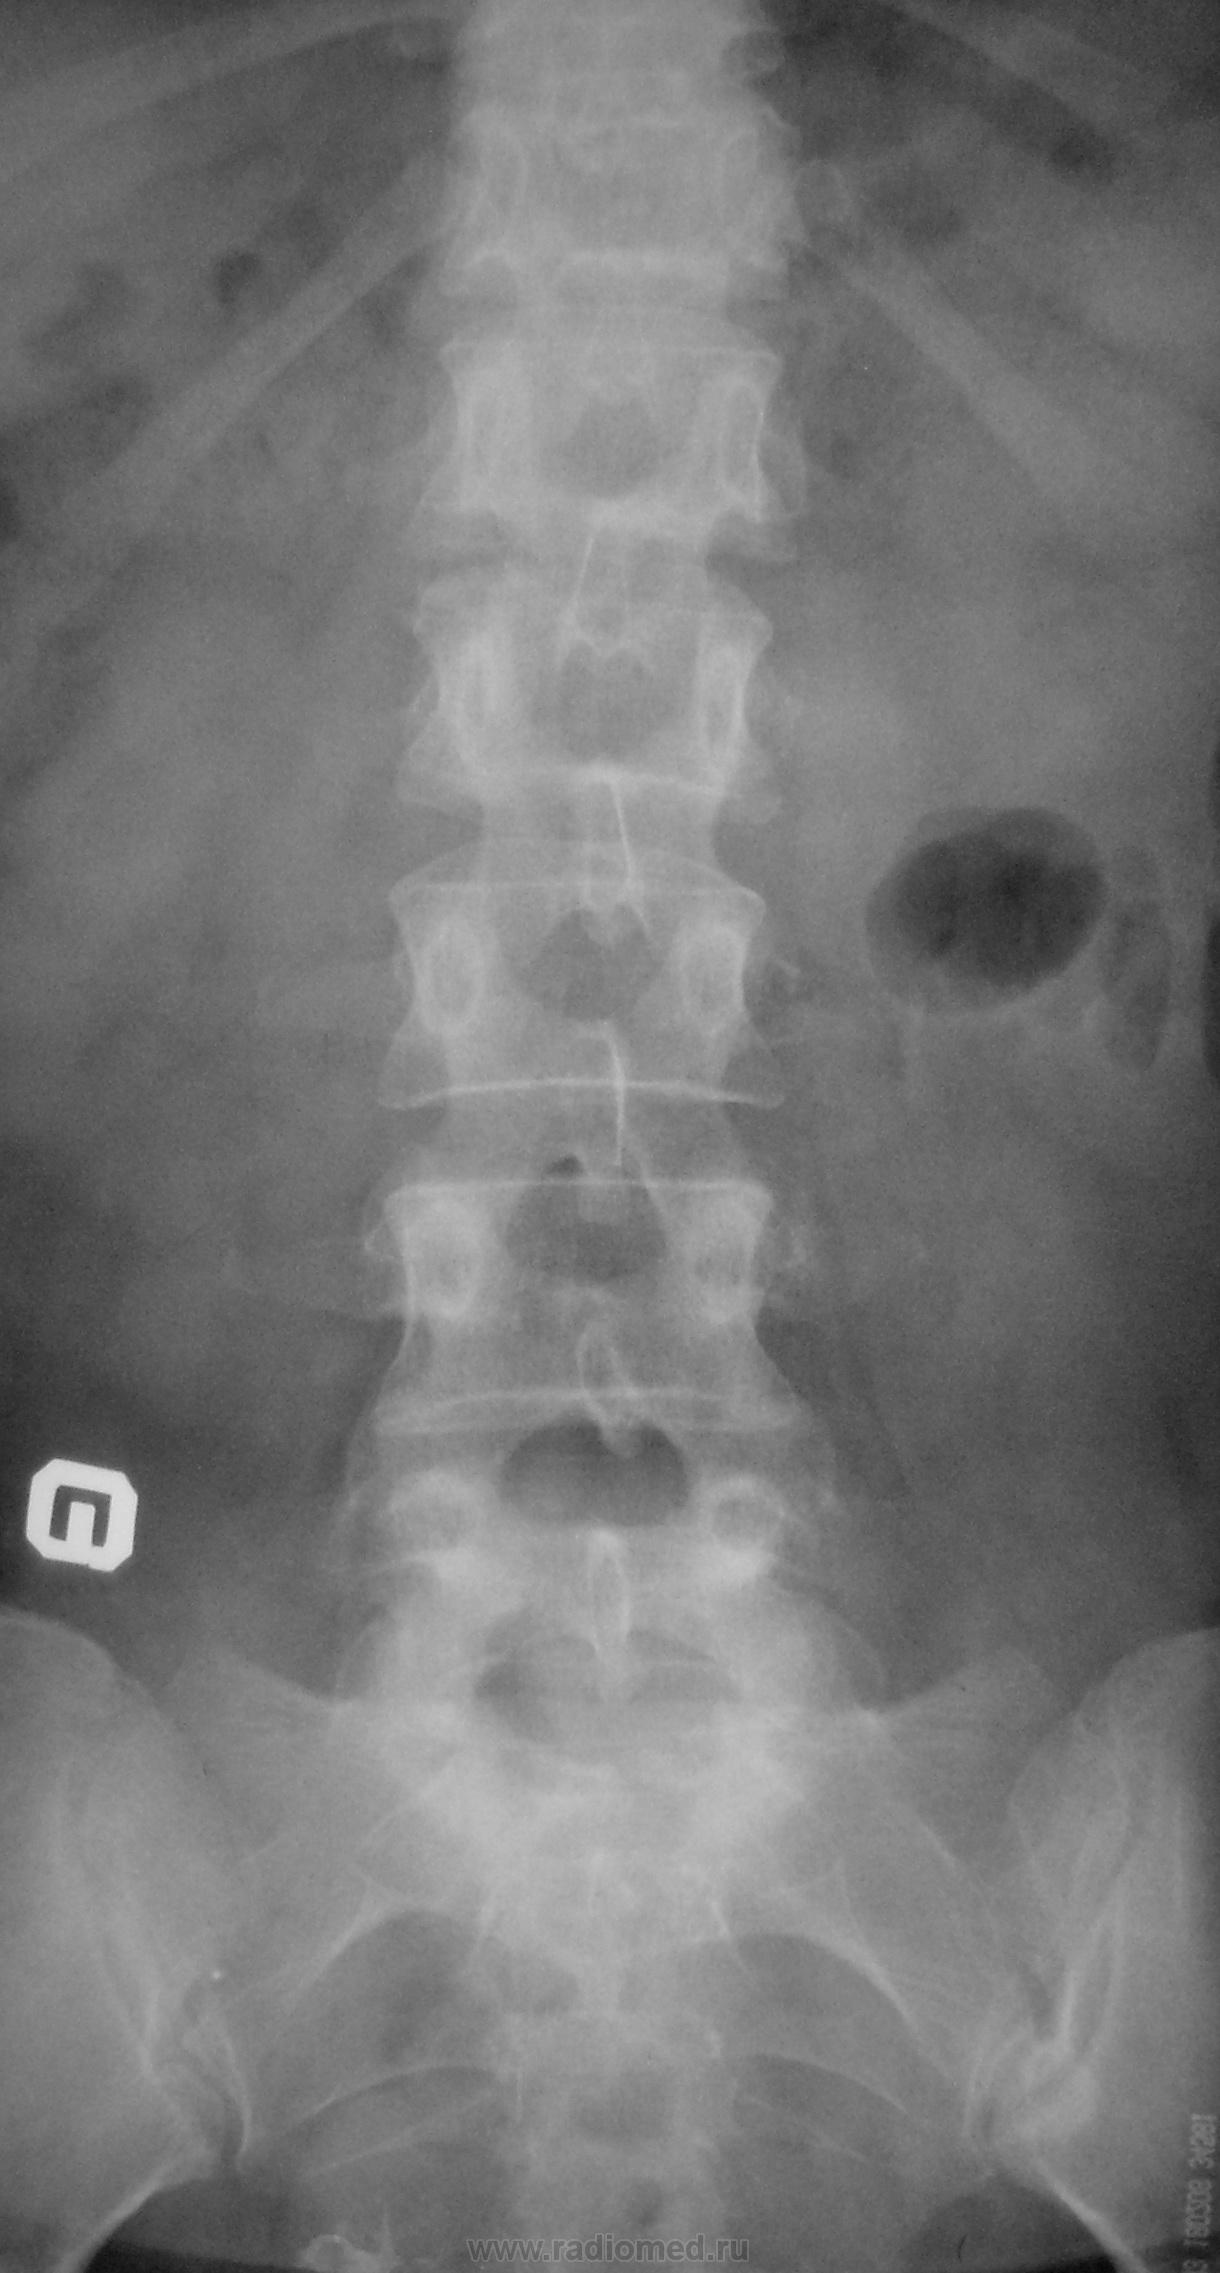

Пол пациента: Женский пол Тип патологии: Врожденная патология Область исследования: Скелетно-мышечная система Методы исследования: Rg Молодая женщина пришла на снимок поясничного отдела. Другая женщина, которая занимается рукопашным боем, обратилась с жалобами на боли в пояснице, после неудачного броска. https://radiomed.ru/sites/default/files/styles/case_slider_image/public/user/712/sl274202.jpg?itok=nrVgJub5 https://radiomed.ru/sites/default/files/styles/case_slider_image/public/user/712/sl274211.jpg?itok=ON6uvgKI https://radiomed.ru/sites/default/files/styles/case_slider_image/public/user/712/sl274212.jpg?itok=NmuMvaE1 https://radiomed.ru/sites/default/files/styles/case_slider_image/public/user/712/sl274213.jpg?itok=nP2dg6tE ID:18475 Пт, 27/01/2012 - 18:10 #1 Фаина Не на сайте Был на сайте: 2 года 11 месяцев назад Зарегистрирован: 14.12.2008 - 16:51 Публикации: 323 В первом случае, кроме остеохондроза и несросшихся апофизов, честно говоря, ничего критичного" не увидела. А во втором случае, не спондилолиз ли в L5?! Пт, 27/01/2012 - 18:17 #2 Наталия Не на сайте Был на сайте: 8 лет 7 месяцев назад Зарегистрирован: 30.07.2008 - 13:24 Публикации: 538 Во втором случае вероятнее спондилолиз. Пт, 27/01/2012 - 18:25 #3 Глазков Игорь А... Не на сайте Был на сайте: 9 месяцев 1 неделя назад Зарегистрирован: 19.12.2008 - 20:41 Публикации: 1597 Шморля в каудальной части тела позвонкаТ12 Прийди к Себе Пт, 27/01/2012 - 21:15 #4 И.Бондаренко Не на сайте Был на сайте: 3 дня 7 часов назад Зарегистрирован: 13.09.2011 - 22:55 Публикации: 9206 Случай №1. Грыжа Шморля Т12, несросшиеся апофизы L2,5 или обызвествившиеся грыжи дисков. Случай №2. Спондилолиз дужки L5. Ср, 01/02/2012 - 21:08 #5 Natalja Не на сайте Был на сайте: 13 лет 10 месяцев назад Зарегистрирован: 27.01.2012 - 22:08 Публикации: 4 Глазков Игорь Артурович wrote: Молодая женщина пришла на снимок поясничного отдела. Другая женщина, которая занимается рукопашным боем, обратилась с жалобами на боли в пояснице, после неудачного броска. В первом случае смущает L2, травмы не было? Чт, 02/02/2012 - 14:35 #6 Глазков Игорь А... Не на сайте Был на сайте: 9 месяцев 1 неделя назад Зарегистрирован: 19.12.2008 - 20:41 Публикации: 1597 травму отрицает Прийди к Себе

В первом случае, кроме остеохондроза и несросшихся апофизов, честно говоря, ничего критичного" не увидела. А во втором случае, не спондилолиз ли в L5?!

Шморля в каудальной части тела позвонкаТ12

Случай №1. Грыжа Шморля Т12, несросшиеся апофизы L2,5 или обызвествившиеся грыжи дисков.